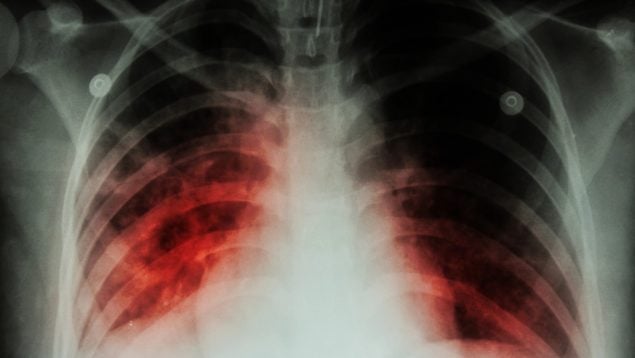

El especialista en enfermedades infecciosas y microbiología clínica Francisco Arnaiz de las Revillas, del Servicio de Enfermedades Infecciosas del Instituto de Investigación Sanitaria Valdecilla (IDIVAL, Cantabria), ha destacado la incorporación de nuevos esquemas orales y abreviados para la tuberculosis resistente.

Francisco Arnaiz ha presentado evidencias prometedoras sobre el uso de nuevos antibióticos frente a infecciones graves por bacterias multirresistentes, y ha explicado que acortar la duración de los tratamientos sin perder eficacia puede ser una estrategia clave para frenar la resistencia antimicrobiana a nivel global.